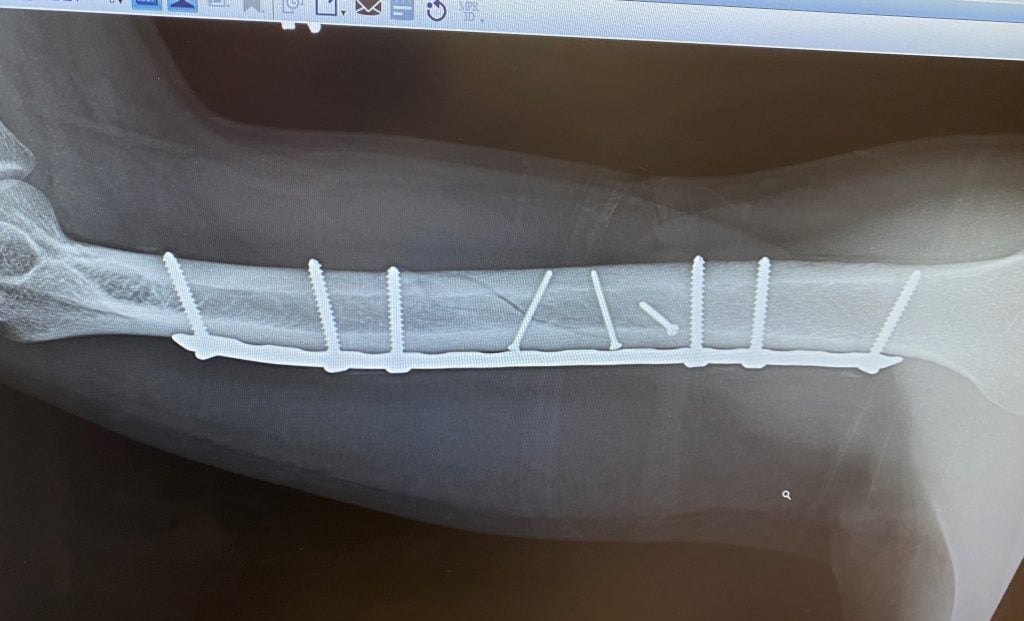

My name is Jayden Cassese and I'm a 12 year old baseball player for the TYA Tigers. In the first pre-season tournament for our big 12U season, I collided with the shortstop sliding into second base and broke off the end of the elbow bone in my left arm. This was the big year for Little League and we had the famous Cooperstown Tournament coming up in July, playing against 100 teams from around the country. I was devastated at the idea of missing that after years of building up to it.

Luckily for us, we knew friends of Dr. Green, and a fellow surgeon at HSS, and both of them strongly recommended we use Dr. Green to repair the elbow. 2 days later I was getting operated on at HSS in Manhattan, and the entire process was handled very well by Dr. Green and his entire staff. After putting 2 pins in my elbow and allowing it several months to heal, while doing PT at HSS along the way, I was able to get back on the field just in time for my big tournament. I came back stronger than ever and hit 2 home runs in one game my first weekend back, then 3 home runs the next week while at Cooperstown! Thank you Dr. Green and team for helping me make it to Cooperstown and beyond.